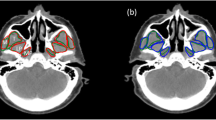

A method is proposed for 3D segmentation and quantification of the masseter muscle from magnetic resonance (MR) images, which is often performed in pre-surgical planning and diagnosis. Because of a lack of suitable automatic techniques, a common practice is for clinicians to manually trace out all relevant regions from the image slices which is extremely time-consuming. The proposed method allows significant time savings. In the proposed method, a patient-specific masseter model is built from a test dataset after determining the dominant slices that represent the salient features of the 3D muscle shape from training datasets. Segmentation is carried out only on these slices in the test dataset, with shape-based interpolation then applied to build the patient-specific model, which serves as a coarse segmentation of the masseter. This is first refined by matching the intensity distribution within the masseter volume against the distribution estimated from the segmentations in the dominant slices, and further refined through boundary analysis where the homogeneity of the intensities of the boundary pixels is analyzed and outliers removed. It was observed that the left and right masseter muscles’ volumes in young adults (28.54 and 27.72cm3) are higher than those of older (ethnic group removed) adults (23.16 and 22.13cm3). Evaluation indicates good agreement between the segmentations and manual tracings, with average overlap indexes for the left and right masseters at 86.6% and 87.5% respectively.

Ng HP, Ong SH, Hu Q, Foong KWC, Goh PS, Nowinski WL: Muscles of mastication model-based MR image segmentation. Int J Comput Assis Radiol Surg 1(3):137–148, 2006

Ng HP, Ong SH, Foong KWC, Goh PS, Nowinski WL: Masseter segmentation using an improved watershed algorithm with unsupervised classification. Comput Biol Med 38(2):171–184, 2008